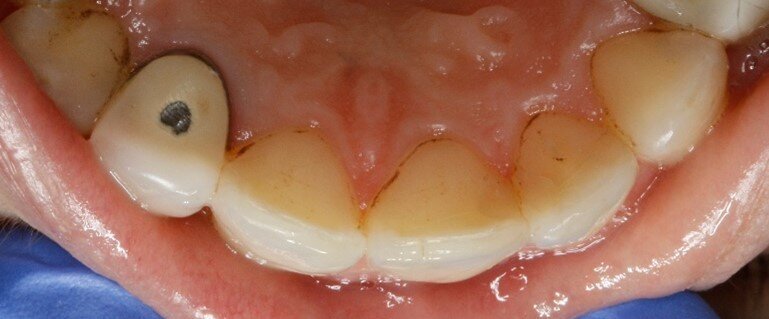

Durante la prima raccolta dati sono stati rilevati 31 siti totali che presentavano black stains (Tab. 4), 13 siti nel controllo ad un mese dall’inizio dell’assunzione di “Lautoselle” (Tab. 5), infine, 18 siti una volta terminata l’assunzione di “Lautoselle” (Tab. 6); di questi ultimi tutti i siti che presentano black stains sono di primo grado e molto meno evidenti rispetto alla prima raccolta dati. Rispetto al caso precedente i risultati sono stati meno soddisfacenti: i siti che presentano black stains corrispondono al 55,8% rispetto a quelli iniziali già al termine del periodo di assunzione di “Lautoselle”. Va in ogni caso considerato che i pigmenti presenti sono molto evidenti e che, per ammissione del paziente stesso, l’assunzione del probiotico non è stata scrupolosa (Figg. 5a-5c).

Fig. 5a - Fotografia del quarto sestante linguale al primo rilievo delle black stains.

Fig. 5b - Controllo dopo un mese.

Fig. 5c - Controllo a tre mesi.

Rispetto al caso precedente i risultati sono stati meno soddisfacenti: i siti che presentano black stains corrispondono al 55,8% rispetto a quelli iniziali già al termine del periodo di assunzione di “Lautoselle”. Va in ogni caso considerato che i pigmenti presenti sono molto evidenti e che, per ammissione del paziente stesso, l’assunzione del probiotico non è stata scrupolosa.